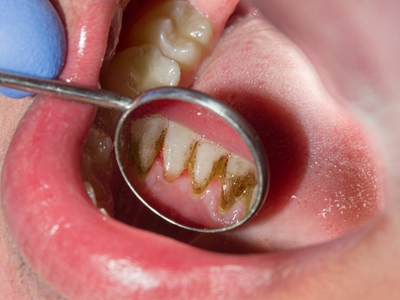

牙龈退缩牙根暴露出现黑斑图

牙龈退缩患者的上排多颗牙齿处的牙龈出现回缩,从而导致牙根外露,外露的牙根上存在黑色的牙菌斑、牙结石,伴有口臭、牙根面敏感等症状。